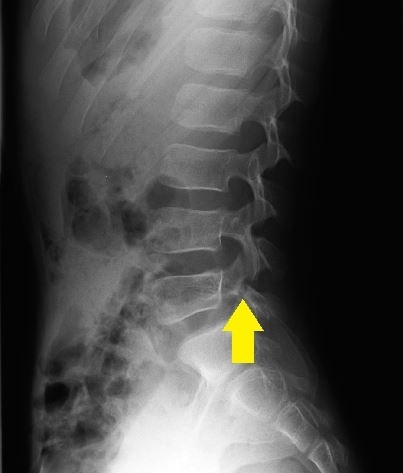

画像検査・診断について

単純レントゲン検査で椎弓・骨年齢の確認、

MRIでは腰椎分離症早期診断を、CT検査(他院依頼)では病期の判定を目的とします。

- 単純レントゲン画像 側面像

- MRI画像

- CT画像

L5左は腰椎分離症終末期